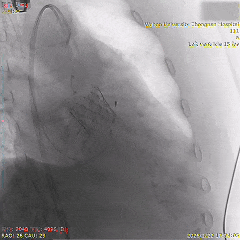

术中影像

瓣膜初始负位定位

第一次瓣膜释放,可见瓣膜轻微向下移动

全展开位评估:左右重合体位造影可见无冠窦侧深度约为瓣下3mm

全展开位评估:左冠切线位造影可见左窦侧深度约为瓣下5mm

为降低起搏器风险,追求更完美精准植入,选择回收重新定位释放

第二次瓣膜稳定释放

全展开位评估:左右重合体位造影可见无冠窦侧深度约为瓣下1mm

充分评估后选择脱钩,瓣膜稳定释放,无二次位移

最终造影可见瓣膜形态佳、位置理想,冠脉良好,无明显瓣周漏